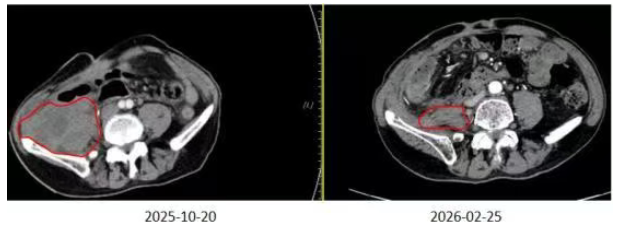

2.影像科对比

1. 简要病史:患者杨某某,男性,54岁,主因“腹膜后粘液纤维肉瘤术后9年,反复复发4次”入院。2016-10在兰大二院因右下腹肿物行微创手术,术后病检结果提示:(腹部肿瘤)肿瘤大小6cm×4cm×3cm,考虑粘液纤维肉瘤,2级。术后行6周期AC方案全身静脉化疗。2018-06-27复查PET-CT结果提示:右侧腰大肌右旁及前缘分别见大小约25.2mm×27.8mm、19.7mm×18.5mm结节影,考虑转移,行微创手术,术后口服安罗替尼靶向治疗半年,期间复查病情稳定。2023-10在兰大二院复查结果提示复发。2023-12在中山大学附属医院行盆腔肿物穿刺病检提示:诊断为间叶源性恶性肿瘤,倾向为纤维肉瘤。2024-01-05行开腹手术。2025-03在兰大二院复查结果提示复发。2025-03-17在西京医院行全麻下右半结肠切除+腹膜后肿瘤切除+腹腔广泛粘连松解术,术后病理:(右半结肠+腹膜后肿瘤切除标本)粘液纤维肉瘤。2025-09-11在西京医院复查结果提示右侧髂肌、腰大肌区占位,考虑复发可能,2025-09-18在全麻下开腹手术(具体不详)。2025-10-09在永登县人民医院查腹部彩超结果提示右下腹两个低回声包块,其一大小5.8cm×3.5cm,其二大小5.0cm×2.5cm。后就诊于我科,于2025-10-28开始行盆腔转移瘤碳离子放疗,处方剂量:PTV: 44Gy(RBE)/11Fx,PTVboost1: 12Gy(RBE)/3Fx,PTVboost2:4Gy(RBE)/1Fx,PTVboost3:16Gy(RBE)/4Fx,放疗期间给予“盐酸安罗替尼胶囊12mg 口服 1次/天”靶向治疗。